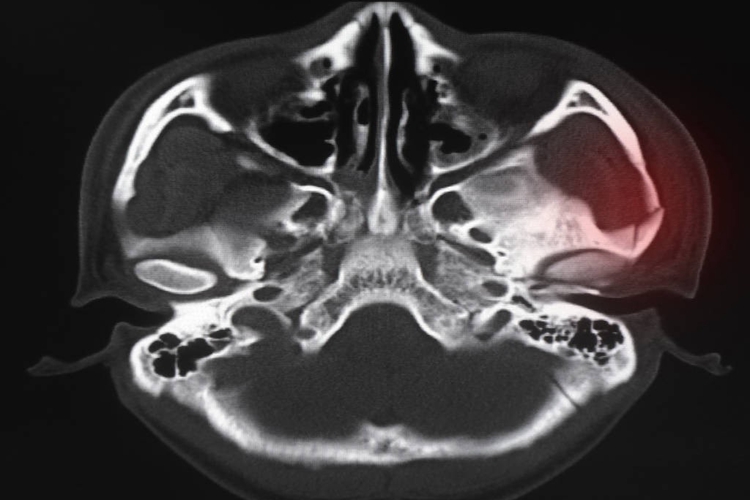

颧骨骨折:颧骨骨折多发生内陷,移位面部塌陷。骨折移位后,因眼球移位、外展肌和下斜肌受累致眼球运动受限而出现复视。颧骨眶壁有闭合性骨折时,眶周皮下眼睑和结膜下可有出血性瘀斑。如损伤面神经额支,则发生眼睑闭合不全。颧骨骨折时常可合并上颌窦外侧壁损伤,窦内出血常从鼻腔流出。